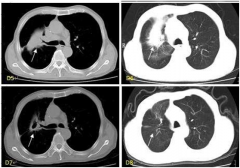

【患者病情介绍】 黄凤玲,50岁,患者因确诊右中上肺中央型肺癌2月余于2015年7月26号入院,曾做过肺部穿刺活检报告(1708791)示:(右肺)肺浸润性腺癌,同时还有骨多发转移瘤,右 [阅读全文]